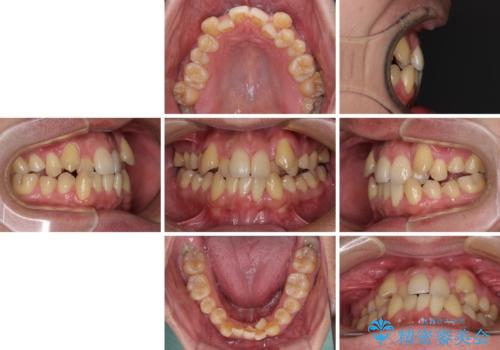

八重歯とクロスバイト 目立たないワイヤー装置で矯正治療

- 八重歯と前歯のクロスバイトを改善したいとのことで来院された患者様です。

マウスピース矯正での自己管理には自信がないとのことで、ワイヤー装置による矯正治療を行うこととしました。

デコボコの程度は強かったのですが、口元の突出感はなかったため、非抜歯矯正としました。